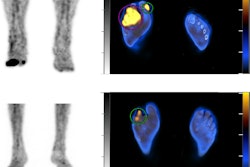

According to the findings, six out of the 14 (42.8%) children showed perfusion defects on Tc-99m MAA-SPECT/CT scans, without morphological alterations on coregistered CT.

Lung SPECT/CT scans with technetium-99m (Tc‐99m) macroaggregates (MAA) in three children with long COVID-19. No significant lung perfusion alterations were detected in a patient with long COVID-19 symptoms (A, D, F) on both axial hybrid images and functional slices (A, D). Conversely, imaging showed an area of mild hypoperfusion in the apical segment of the right upper lobe, clearly evident on both axial fused and functional slices in another patient (B, E; arrow). Finally, an area of moderate hypoperfusion was detected on a third patient, clearly evident on hybrid imaging, as well as on the functional slices (C, F; arrow), which is associated to a diffuse and heterogenous distribution of radiotracer in both lung parenchyma (*). All these abnormal findings do not correspond to parenchymal alterations on coregistered CT images (G, H, I). Image and caption courtesy of Pediatric Pulmonology through CC BY 4.0.Five of these six children were previously affected by a mild acute infection while one was asymptomatic during SARS-CoV-2 infection, the authors noted. During the follow-up, however, persisting symptoms (e.g., headache and shortness of breath during exercise) were detected in all six.

In addition, among children with abnormal finding on Tc-99m MAA-SPECT/CT, two were probably infected with wild virus, two with alpha, one with delta, and one with omicron, the team reported.